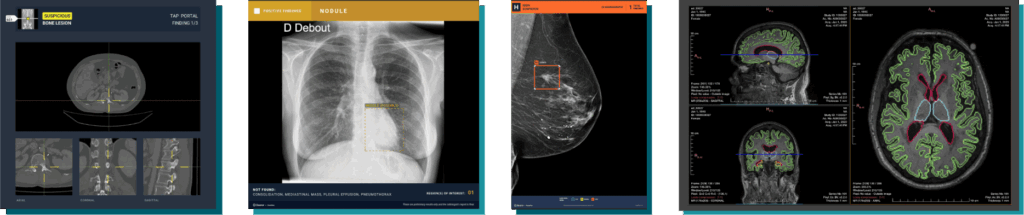

Désormais, tous les centres de notre réseau peuvent bénéficier de Gleamer CoPilot, une suite de solutions IA pour les seconder dans leurs examens de radiologie générale, de scanner et d’IRM. Nous sommes convaincus que ce type de logiciel de radiologie novateur est un véritable atoût pour nos radiologues. Cette solution complète couvre de nombreux examens et accompagne nos médecins dans leur quotidien. L’IA permet de renforcer la fiabilité des diagnostics et d’assurer le meilleur suivi à nos patients.

Les radiologues de notre réseau ont accès à de nombreux logiciels Gleamer, notamment les modules historique de notre partenaire :

- BoneView : Détection de traumatismes osseux et fractures.

- ChestView : Détection d’anomalies et de pathologies sur des radiographies thoraciques.

- BreastView : Aide à la détection précoce de cancer du sein.

- Pixyl.Neuro : Détection de troubles neurologiques.

- LungCT : Détection de nodules pulmonaires.

- BoneCT : Détection de lésions osseuses.